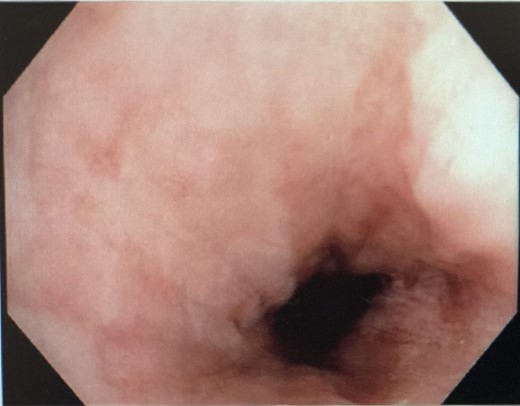

He was kept nil orally. Analgesia, antiemetics, IV proton pump inhibitor, and empirical IV antibiotics were commenced. Esophagastroscopy showed large hiatus hernia with reflux esophagitis. Middle-lower third esophagus appeared patchy, gangrenous from 27 cm to gastroesophageal-junction at 35 cm (Fig. 2). Multiple biopsies for viral culture and microbiology showed chronically inflamed cell infiltrates consistent with mucosal ischemia. No viral inclusions are seen. At the end of procedure, a PEG with jejunal extension tube was inserted to commence feeds.

Interval gastroscopy in 2 weeks showed healing mucosal ischemia with slough from 27–30 cm (Fig. 3). Clear fluids were commenced and gradually upgraded to normal diet. Follow-up CT showed no contrast extravasation within posterior mediastinum (Fig. 4) and gastroscopy in 8 weeks showed healed esophagus.

Healing mucosal ischemia from upper, mid and distal esophagus.